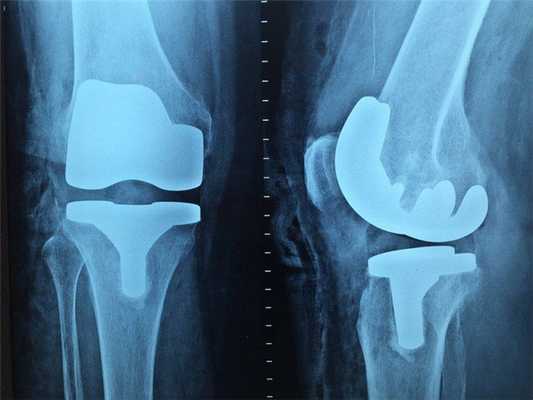

Рентген

Наиболее старый и привычный метод визуализации человеческого тела. Применяют рентген повсеместно, от хирургии до стоматологии. Метод прост и понятен: человека облучают особыми лучами, которые легко проходят сквозь мягкие ткани и задерживаются в твёрдых. Благодаря этому принципу, на фотоплёнку или датчик, расположенные на противоположной от источника лучей стороне, передаётся изображение, а в распоряжение врача попадает рентгенография или рентгеноскопия.

Главные плюсы такого обследования: быстрота и стоимость. Рентгеновскими аппаратами оснащены практически все больницы, процедура проходит быстро и стоит недорого.

Главные минусы: облучение и качество изображения. При проведении рентгенографии пациент облучается, а картинка получается двумерной. Врач с трудом может разглядеть внутренние органы по отдельности, поскольку их тени перекрывают друг друга. Также невозможно детально разглядеть хрящевую ткань и мозг. Хрящи практически не задерживает лучи, мозг надёжно закрыт черепной коробкой. Для их исследования рентгенография не подойдёт.

Наиболее эффективно будет проводить рентгенографию при повреждениях костей, суставов и зубов.

Что покажет рентген

Рентген - это самый широко доступный тип обследования. В Санкт-Петербурге его можно сделать быстро на платной или бесплатной основе как в частных, так и в государственных клиниках и больницах. Основная задача рентгенографии - дать общее представление об изменении структуры органов и костной ткани. С помощью рентген-аппарата врач может хорошо визуализировать:

Основное преимущество рентгенографии заключается в том, что это быстрый и дешевый метод сканирования. Однако по точности и диагностической ценности он безусловно уступает как УЗИ, так и таким высокотехнологичным методам исследования, как МРТ и КТ.

В основе физики работы рентген-аппарата лежат просвечивающие способности рентгеновских лучей. Получение плоского двухмерного изображения основано на ослаблении рентгеновского излучения при его прохождении через различные ткани. При рентген-сканировании пучок излучения, проходя через ткани организма, которые обладают различной плотностью, рассеивается и тормозится. Таким образом, на пленке возникают изображения разной степени интенсивности. Лучевая нагрузка при рентгенографии небольшая, но она всегда есть и может составлять от 0,1 до 1 мЗв. Поэтому рентгенография запрещена для беременных женщин, а здоровому человеку рентген можно делать 1- 2 раза в год.

Кроме дозы облучения у рентгеновского сканирования есть один существенный диагностический недостаток - плоская картинка. Поскольку рентген изображения - это тень ткани на пленке, объемно оценить органы и структуры человеческого тела с помощью рентгена не получается.

Рентгенография

Принцип работы рентгеновского аппарата заключается в том, что рентгеновские лучи, проходя через разноплотную среду исследуемой области, по-разному ослабляются: более плотная костная ткань в значительной степени поглощает рентгеновское излучение, менее плотная подкожно-жировая клетчатка ослабляет его в небольшой степени, а воздух, содержащийся в околоносовых пазухах или легких, не задерживает совсем. Эти неравномерно ослабленные пучки рентгеновских лучей, попадая на светочувствительный слой пленки, формируют рентгенограмму — изображение, которое отображает все структуры исследуемой области, наслаивая их друг на друга. При этом получаемый снимок позволяет определить форму, размеры и строение исследуемой области, выявить или заподозрить структурные нарушения, а исследование в двух или нескольких проекциях позволяет определить локализацию выявленных изменений. Чаще всего рентгенография используется для исследования костей, легких, почек, кишечника.

C самого начала существования этот метод диагностики вызывал у пациентов множество вопросов по поводу воздействия рентгеновского излучения на организм. На сегодняшний день специалисты подтвердили вред рентгена и его способность влиять на развитие нежелательных процессов в организме. Тем не менее, этот метод лучевой диагностики продолжает пользоваться спросом, поскольку требует минимальных затрат.

Мы также всегда делаем КТ пациентам с подозрением на нарушение мозгового кровообращения, исследование позволяет не только подтвердить диагноз, но и оценить «масштаб» поражения и выработать верную тактику. Назначают его при патологии почек, в частности, при наличии камней. На томографе можно увидеть их расположение, оценить плотность и структуру, а значит, принять решение об операции или выборе консервативных методов. МРТ имеет преимущества при изучении патологий суставов, для диагностики заболеваний головного мозга, спинного мозга, органов малого таза.

Доза радиологического облучения при КТ значительно выше, чем при рентгеновском исследовании, не стоит «бить из пушки по воробьям». К примеру, при подозрении на перелом или при первичном обращении с болью в суставах предпочтительнее сделать рентген.